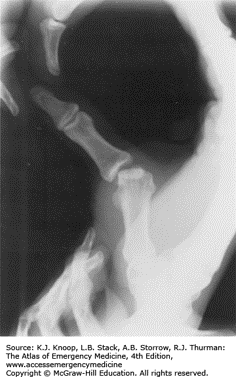

Wrist: Kienbock Disease

Pathophysiology: AVN/osteonecrosis of the lunate > leads to collapse

Causes: result of trauma/injury, abnormal vascular diseases OR by unequal radius and ulna lengths

Physical Exam:

X-rays

MRI